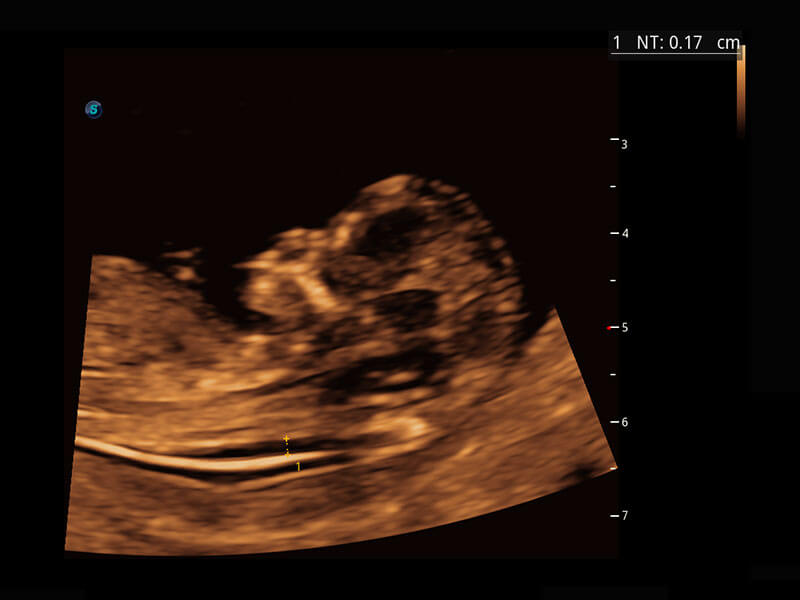

P60提供简单易学易用的高端诊断工具,为您中晚孕筛查提供快速清晰的解剖信息。

S-Fetus能够助您在实时扫查过程中自动识别标准切面、自动测量并录入报告。一个按键,即可快速、高效地获取胎儿生理指标,简化您的产科检查操作。